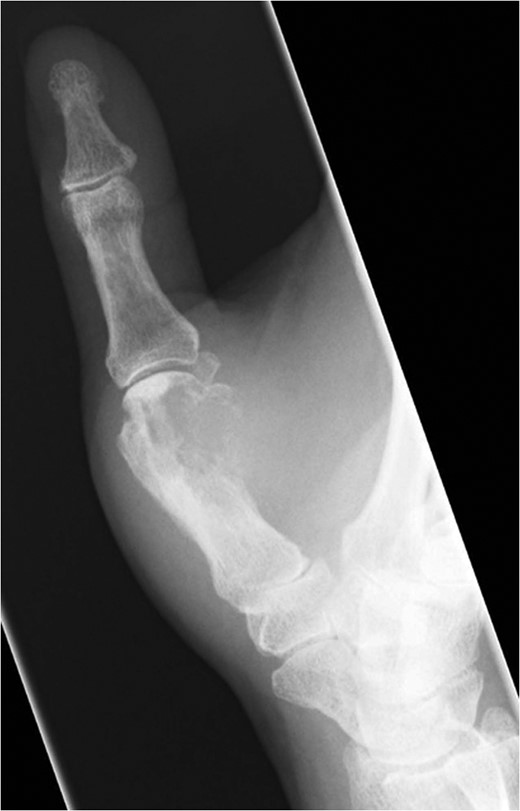

Fifteen months after surgery, the patient presented with redness, pain, and swelling of the right thumb. Radiography revealed right metacarpal bone destruction (Fig. 1). Technetium-99m HDP bone scintigraphy showed strong tracer accumulation in the right thumb (Fig. 2). T1-weighted magnetic resonance images revealed a mass lesion with a contrast effect (Fig. 3). Fluorine-18 fluorodeoxyglucose positron emission tomography also showed abnormal uptake in the right metacarpal bone, with no accumulation at other sites (Fig. 4). Lung and abdominal computed tomography scans showed no distant metastases or recurrence of the primary lesion, and serum tumor marker levels were normal.

Plain radiographic image of right metacarpal bone destruction.